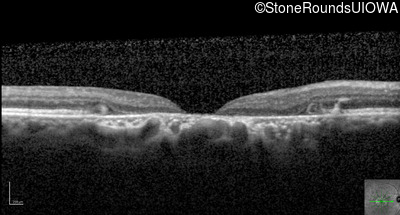

Optical Coherence Tomography - Right - 20/200 sc

Exemplar / OCT Stack

Optical Coherence Tomography - Left - 20/400 sc